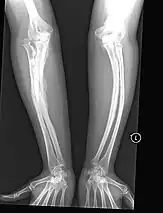

The main symptom of osteogenesis imperfecta is fragile, low mineral density bones; all types of OI have some bone involvement.[5] In moderate and especially severe OI, the long bones may be bowed, sometimes extremely so.[28] The weakness of the bones causes them to fracture easily—a study at the Endocrine Unit at the National Institute of Child Health in Karachi, Pakistan found an average of 5.8 fractures per year in untreated children.[29] Fractures typically occur much less after puberty, but begin to increase again in women after menopause and in men between the ages of 60 and 80.[1]: 486

OI type III causes osteopenic bones that fracture very easily, sometimes even in utero, often leading to hundreds of fractures during a lifetime;[24] early scoliosis that progresses until puberty; dwarfism (a final adult height frequently less than 4 feet or 120 centimetres); loose joints; and possible respiratory problems due to low rib cage volume causing low lung volumes.[5]: 1512

Diagnosis is typically based on medical imaging, including plain X-rays, and symptoms. In severe OI, signs on medical imaging include abnormalities in all extremities and in the spine.[97] As X-rays are often insensitive to the comparatively smaller bone density loss associated with type I OI, DEXA scans may be needed.[5]: 1514